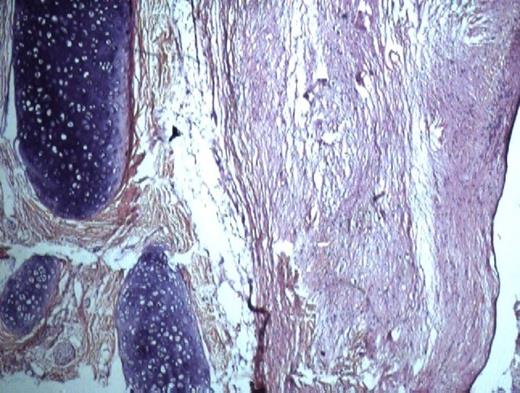

She noticed this swelling 6 months previously, which more recently increased in size. Lately, she experienced difficulty in moving tongue, resulting in globbus sensation and dysphagia. General examination of the patient revealed average built, pulse rate 80 beats/min with regular rhythm, BP 130/90 mm Hg, RR 24 breaths/min. There was no history of fever, night sweats and weight loss. Jaundice, cyanosis and oedema were absent. Computed tomography revealed a 3x2 cm cystic anterior lingual structure, the wall of which was thin and regular with a content consisting of homogenous fluid. There was no bone involvement. With a clinical diagnosis of dermoid cyst an excision biopsy was performed. Histopathological findings consisted of cyst wall lining of stratified squamous epithelium with sebaceous glands, blood vessels, muscle and cartilage in the underlying connective tissue, and a diagnosis of teratoma was made (fig 2). No evidence of malignant transformation was noted. One year after surgical removal of the lesion, there was no sign of recurrence.